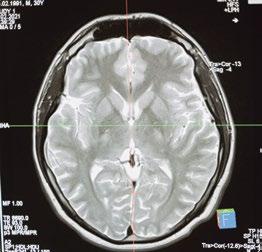

Malpetti et al. (2018) evaluaron la influencia del imc en la neurodegeneración al correlacionarla con el metabolismo cerebral, demostrada por tomografía por emisión de positrones con F-fluorodeoxiglucosa (18f-fdg-pet). Esta evaluación comprobó que las mujeres con mayor imc tienen mayor vulnerabilidad a la alteración en los sistemas neuronales y una conectividad reducida en las redes cerebrales frontales y límbicas.

Por otra parte, estudios con resonancia magnética han evidenciado que la alteración en la bhe en el hipocampo puede indicar un evento temprano, y una cascada patológica en la ea, involucrando la disminución de flujo sanguíneo cerebral (fsc), la pérdida de bhe y la inflamación. Aún quedan por estudiar estas vías, pero se tiene claro que la hipoperfusión y el incremento de la fuga de la bhe encajan en el circuito de retroalimentación positiva hipotética del aumento en la fuga de bhe cuando el líquido cefalorraquídeo disminuye y viceversa (Walker et al., 2017). De hecho, la hipoperfusión puede estar implicada con el deterioro cognitivo y la disminución del volumen del hipocampo. Esta fuga también se ve aumentada con una dag porque se exacerban los efectos del envejecimiento sobre la permeabilidad de la bhe (Walker et al., 2017).